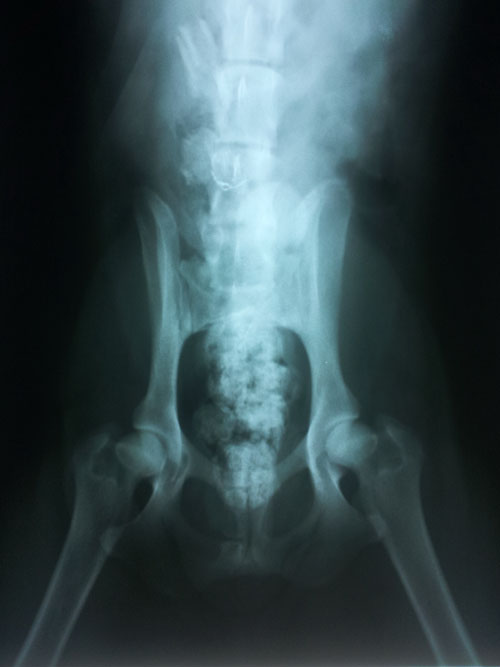

HD - Normal